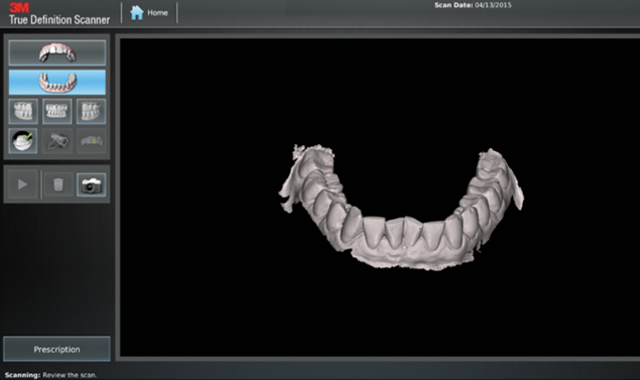

We scanned the upper and lower arches capturing all incisal edges, occlusal surfaces, interproximal embrasures, distals of terminal molars and 3 mm of gingival margins (Figs. 4-7). There was no need to scan the bite. We submitted the scans to Align by completing the prescription on the True Definition scanner (Fig. 8).

Fig. 6

Fig. 7